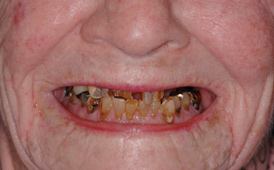

Fig 8. Failing dentition in an 82-year-old patient currently diagnosed with tardive dyskensia.

Figure 8

Fig 9. Transition line could not be hidden due to uncontrolled contortions of the facial musculature.

Figure 9

A patient with tardive dyskensia, for example, may experience dramatic changes in expressive facial activity and corresponding dysfunction in the muscle memory needed to repeat a centric position.19,20 Figure 8 and Figure 9 show an 82-year-old patient who had previously been treated for depression, had a failing dentition, and was diagnosed with tardive dyskensia. Extreme uncontrolled contortions of the facial musculature were evident in the patient when attempting to record a high smile line; removal of enough maxillary bone to hide the transition line was impossible. Dramatic compromises in occlusal scheme may be necessary to achieve even a moderately successful result; yet the implant approach realistically may be the only way to offer any functional improvement (Figure 10 and Figure 11).